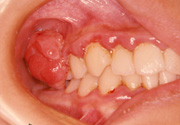

エプーリス

一見、がんではないかと思われるかも知れませんが、口腔外科専門医ならまず誤診することはないでしょう。

この症例はエプーリスという良性の、しかも歯周病を原因として発症したもので、原因の歯の処置を含めて切除すれば治癒します。

このほかにも一見腫瘍のように見えて、実はそうでない腫瘍類似病変、あるいは「がんもどき」ともいえる病変が口の中にはよく見られます。